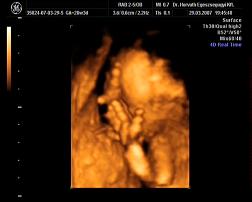

Mi meg megjöttünk az uh-ról, Ákosom nagyon szégyenlősvolt, már ami a kis arcát illeti, mert végig az arca előtt volt mindkétkeze, dörzsölte a szemét....néha profilból el lehetett kapni egy-egy pillanatot, szerintem gyönyörű...már olyan babás! Bezzeg a kukacát, azt mutogatta szorgosan! Meg megmutatta a kezeit, lábait, és hát néha a kis arcát is ki lehetett venni, de szemből teljesen most nem mutatta meg magát. De ami a legfontosabb, minden a legnagyobb rendben Vele, a gerince gyönyörű, gyomortelítődés szépen látható, vesék is szépek, koponya rendben....szóval minden okés, és ez a lényeg. Már 31O gramm a kis Drágám! Nagyon jó volt az egészvizsgálat, csak azt sajnálom, hogy nem sikerült képet készíteni Róla, pedig a doki mindent megtett...deDVD-t kaptunk, majd abból megpróbálok valamit kiügyeskedtetni Apával.

tegnap varézsoltam ki Nektek a DVD-ről olyan képeket, ahol nagyjából látszik Ákosom, erre elment a net... :evil: Űgyhogymost megpróbálom felrakni, aztán írok. :D

Elsőnek egy profil Kép

Apa "büszkesége" :D Kép

Kép